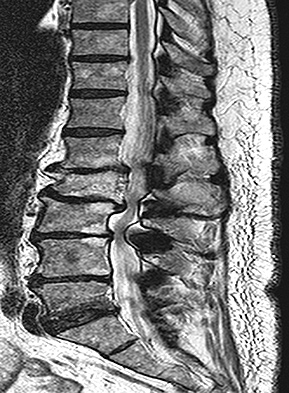

Figures 1 through 3 show sagittal and axial MRIs and a radiograph from a

77-year-old woman with leg pain when standing and walking of 1 year duration. The pain improves when she leans forward. She has been in physical therapy, taken oral analgesics, and had epidural injections with minimal relief. What is the best next step?

The patient has lumbar stenosis of L2-3 and L3-4. She has no spondylolisthesis or instability. For her condition, spinal fusion plays a minimal role. She has no evidence of instability, and her condition can be addressed through laminectomy only. No role exists for microdiskectomy, because her disease results from a combination of ligamentum flavum hypertrophy and facet hypertrophy.